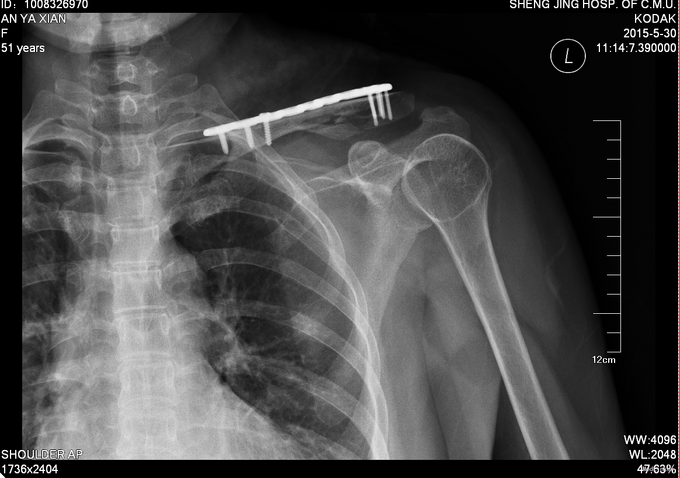

患者入院后完善检查,无血气胸,单纯锁骨骨折,择期行左锁骨粉碎性骨折切开复位内固定术,术后患者患肢悬吊中。术后患者14天拆线后出院。